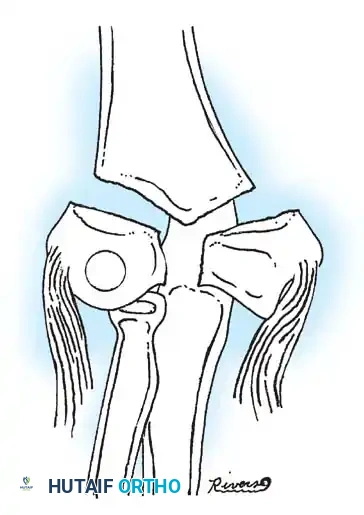

Fractures can present as angulated, translocated (shifted), or totally displaced. In the context of an elbow dislocation, the proximal fragment may become loose within the joint space or trapped, acting as a mechanical block to reduction.

Fig. 33-40 Examples of angulation, translocation, and total displacement of radial neck fractures.

ADVANCED RECONSTRUCTION: ULNAR OSTEOTOMY FOR CHRONIC DISLOCATIONS

In cases of chronic radial head dislocation (often missed acutely or associated with plastic deformation of the ulna), simple open reduction is insufficient. The Hirayama Technique utilizes an ulnar osteotomy to overcorrect the angular deformity, thereby pulling the radial head back into the joint via the interosseous membrane.

TECHNIQUE 33-5: Osteotomy of the Ulna (Hirayama et al.)

- Preparation: Inflate a pneumatic tourniquet. Make a posterolateral skin incision exposing the radiohumeral joint and proximal third of the ulna. Excise intra-articular scar tissue.

- Osteotomy: Perform a subperiosteal osteotomy of the ulna 5 cm distal to the olecranon.

- Distraction and Angulation: Distract the osteotomy by 1 cm to lengthen the ulna.

- For Anterior Dislocation: Correct by posterior angulation of the ulna.

- For Lateral Dislocation: Correct by medial angulation of the ulna.

- Fixation: Secure the osteotomy with a metal plate bent to approximately 15 degrees. Ensure the radial head rests perfectly within the radial notch of the ulna without excessive radiocapitellar pressure.

- Closure: Approximate the anconeus. Do not repair the annular ligament, as this can restrict rotation.

- Postoperative Care: Apply a plaster splint in 90 degrees of flexion and full supination for 4 weeks, followed by aggressive active range of motion.

Fig. 33-36 Overcorrection with posterior convexity for anterior dislocation.

Fig. 33-37 Overcorrection with medial convexity for lateral dislocation.